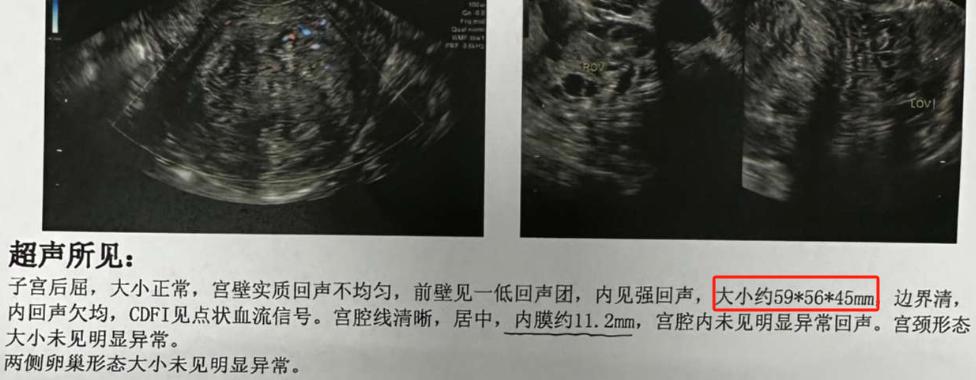

计划备孕,子宫肌瘤5.9*5.6*4.5,寻求治疗和备孕方案。